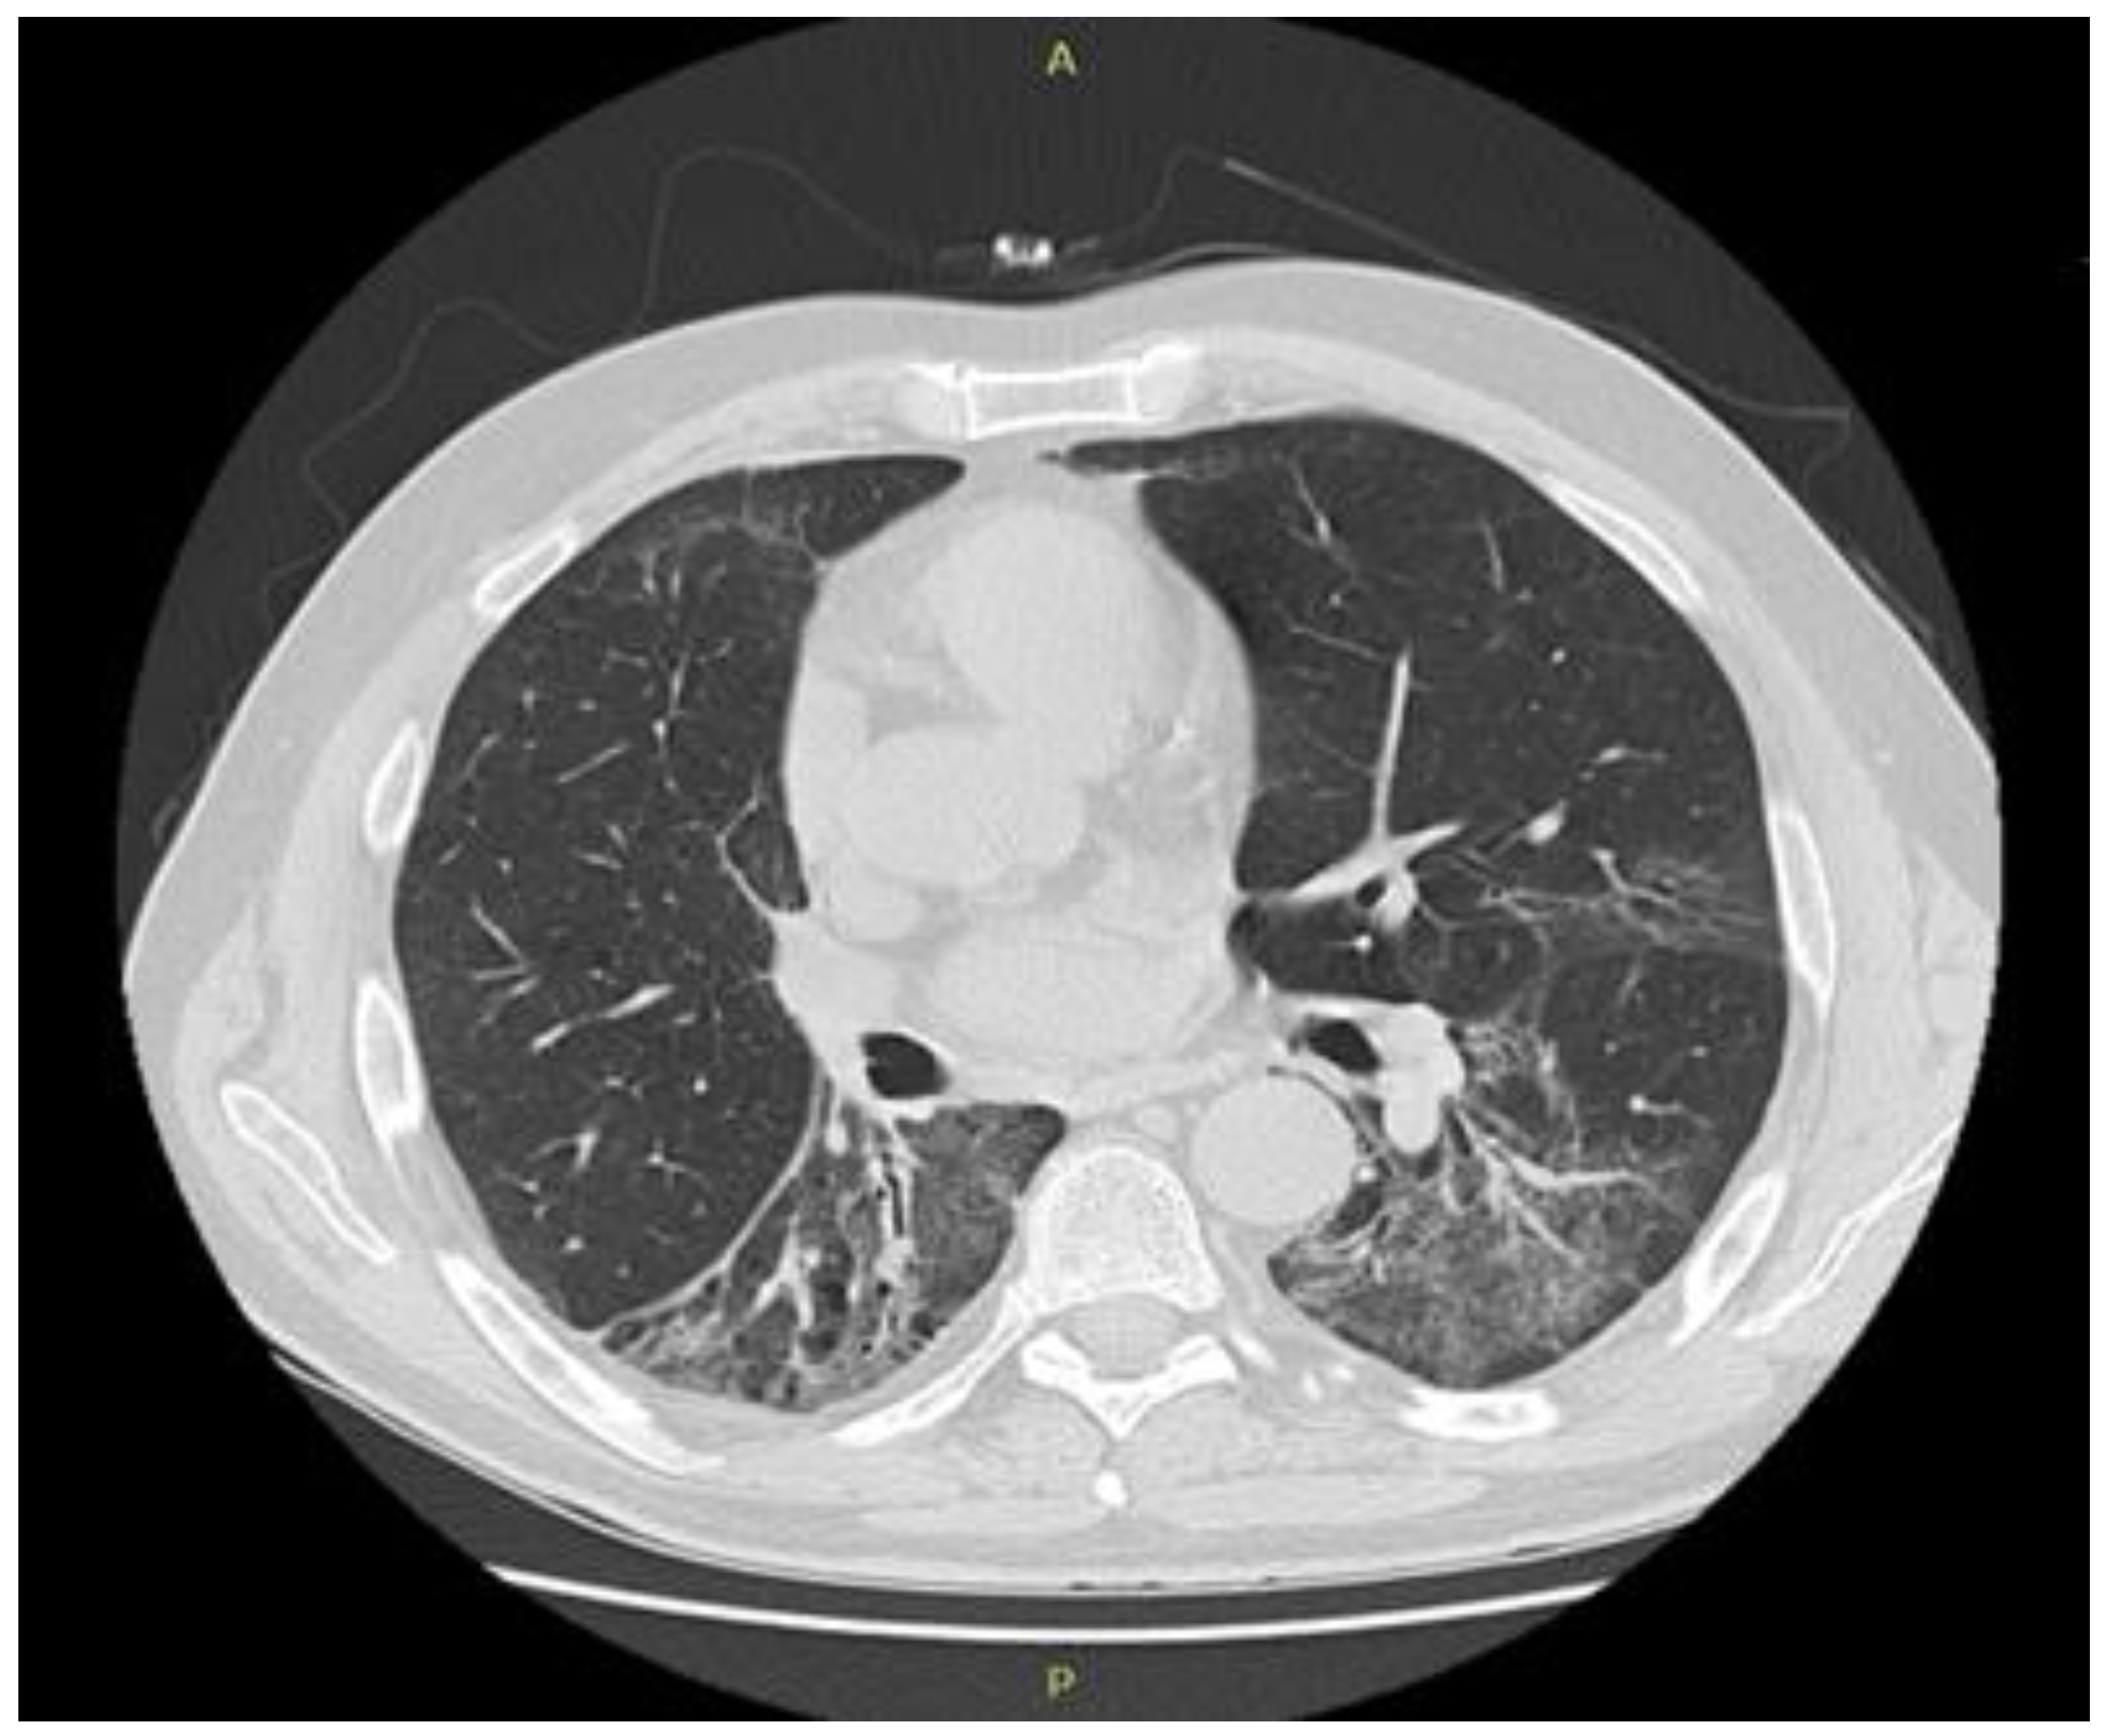

5. ICI Therapy-Related Pneumonitis